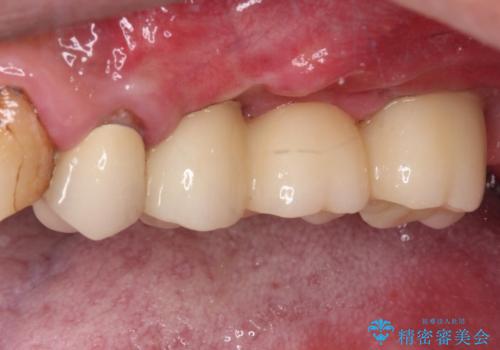

左側は大臼歯2本と小臼歯1本が欠損しているため、インプラント2本を治療したブリッジ、右側は中間欠損であり、前後の歯も加療が必要であったためブリッジによる補綴治療を行うこととしました。

治療後の現在は、より長い期間安定した状態を維持していただくため、就寝時マウスピースを装着するようお願いしております。